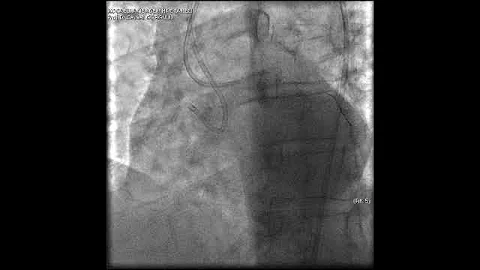

Complex Pci For Rca Cto With Bifurcation At Distal Cap Video 7